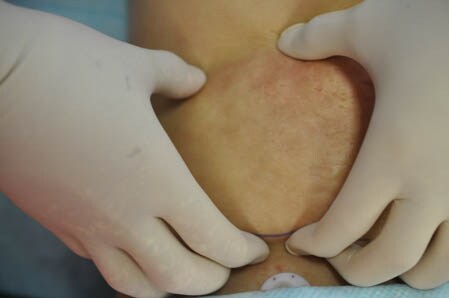

上記の画像の部分をつまんでみましょう。

↓ ↓ ↓

同様に下腹部も見ておきましょう。